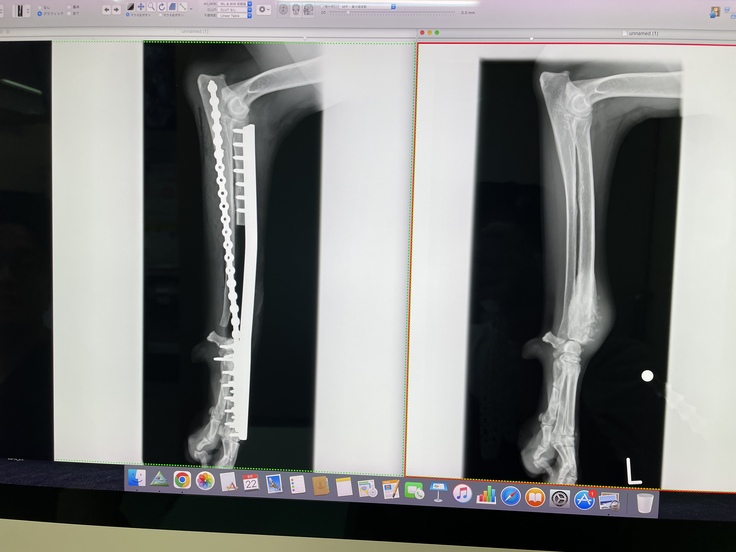

日本では断脚が一般的だけど、アメリカでは18件、部分的に骨を取ってプレートで固定するサルベージ手術をした例がある。

日本では正直施術例は聞いた事がないけど、それをモカに施術するのはどうか?

それでも私達は5歳という年齢も考え、モカの残りの人生を自分の脚で歩いて生活が出来る可能性に賭けたいと思い、サルベージ手術をお願いし、9月20日にサルベージ手術を無事に終える事ができました。

(左側が術後のレントゲンです。)